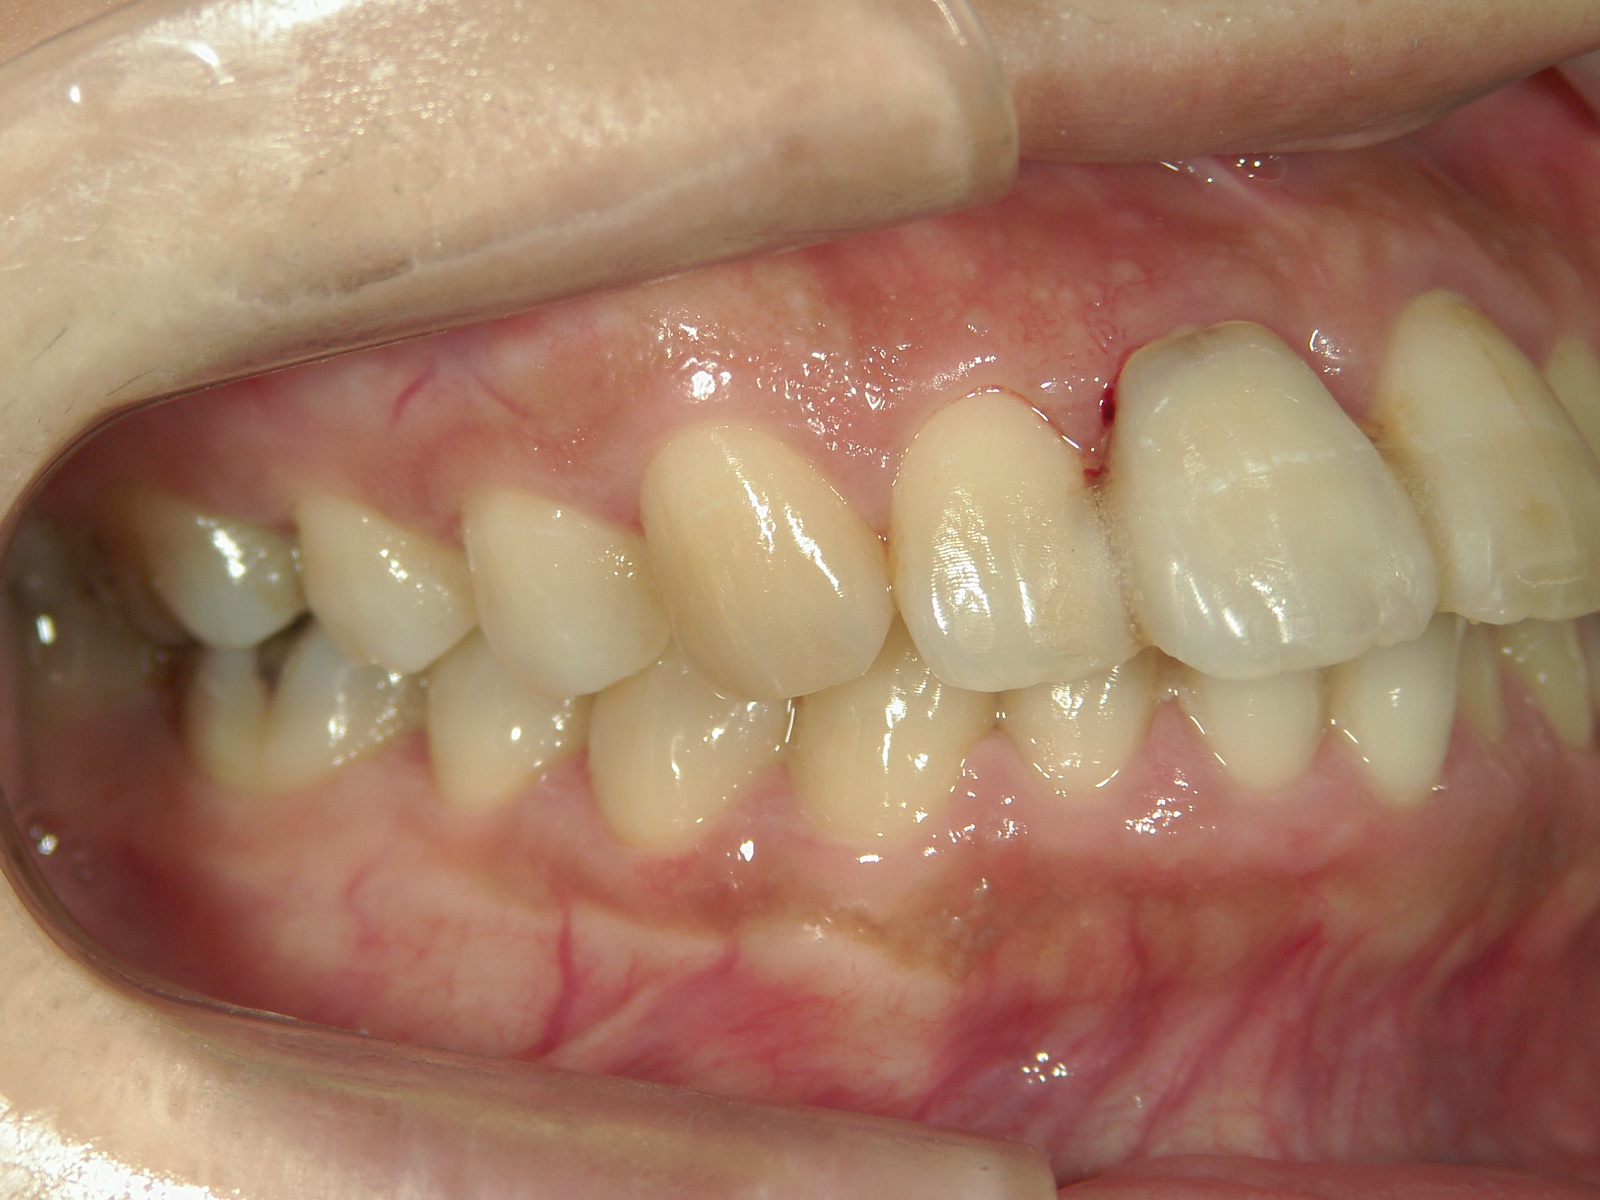

歯根の移動後、元々の中切歯の形に硬質レジンで歯冠を形態修正しました。

終了後に歯肉を形態修正しました。

・右上犬歯を移動して、開いたスペースへ移動。

・右上 第一小臼歯を移動して犬歯のスペースへ移動。